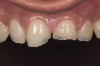

Acid dissolves the palatal enamel of upper anteriors, thus exposing the underlying dentin. This makes teeth appear higher in chroma and leads to hypersensitivity as well as supraeruption of opposing incisors. Clinically, this restricts the space needed to restore lost palatal tooth structure (Figure 1 and Figure 2).

Palatal veneers using a modification of Dahl’s9 principle (Figure 3).

The greatest challenge exists in management of localized TSL on the palatal surfaces of the upper anteriors with little or no TSL on posteriors. The option of palatal veneers using a modified Dahl’s9 principle is conservative and advocated in such cases when possible.